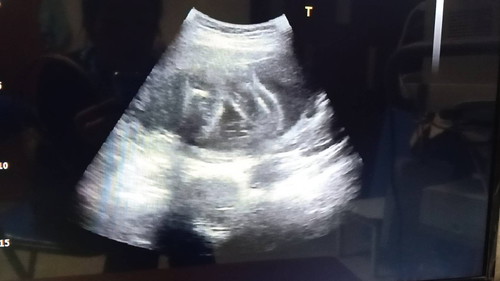

เพศลูก

ซาวด์ครั้งเเรกหมอบอกว่าอาจจะได้ลูกสาวเเต่วันนี้ไปซาวด์ครั้งที่2หมอบอกว่าอาจจะเป็นผู้ชายเพราะว่าเห็นเหมือนมีติ่งอะไรยื้นออกมาเเต่คลอดออกมาจะเป็นเพศใหนเเม่ก้อรัก??